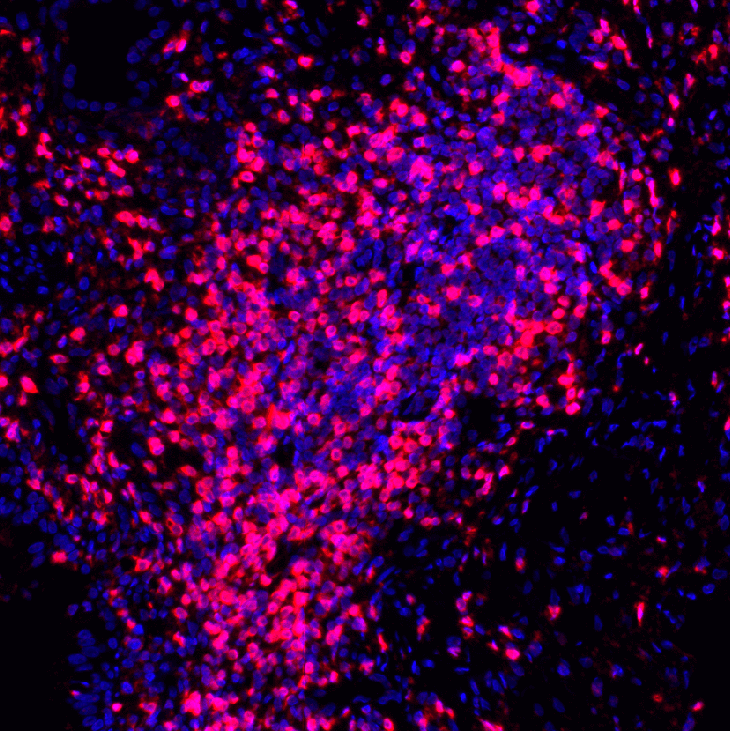

超强大空间分析功能,深入分析挖掘多重荧光免疫组化图像中多维度空间信息

空间关系分析

荧光-TLS AI识别

HE-TLS AI识别